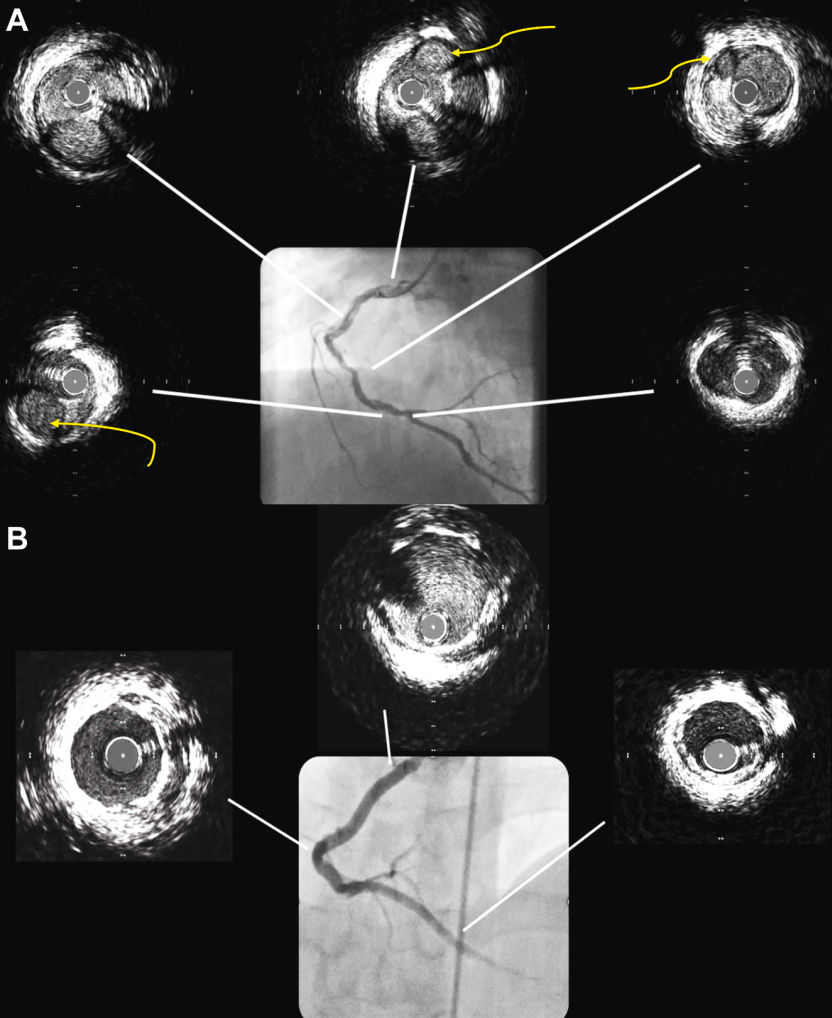

鉴于复杂的解剖结构和降低的LVEF,在IVUS引导下对RCA进行了经皮冠状动脉介入治疗(PCI)。然而,IVUS未能区分SCAD与血栓(图2)。

图2 病例1:RCA 经皮冠状动脉介入治疗(PCI)前后的血管内超声图像

(A)从 RCA 近端到 PDA 可见多个血液充盈的管腔(黄色箭头)。(B)经皮冠状动脉介入治疗(PCI)后血管内超声图像显示支架膨胀良好,以及 PDA 远端节段健康。

图3 病例1:LAD 和 LCX 支架植入前OCT图像

(A)LAD:壁内血肿(∗)、内膜破裂(蓝色箭头)以及管腔被向内推挤。(B)LCX 显示第二个管腔朝向9点至3点钟方向形成(∗),真腔(#)被推向3点至6点钟方向;可见清晰的内膜破口(蓝色箭头)。

随后,对LAD(图3A)和LCX(图3B)进行分期OCT检查,证实了 SCAD,显示出内膜及内弹性膜破裂、壁内血肿和真腔受压(在造影上表现轻微或被遗漏)。OCT 显示 LCX 存在第二个管腔,真腔推移,并有清晰的内膜撕裂。基于OCT诊断,患者随后接受了LCX和近端LAD的PCI治疗。